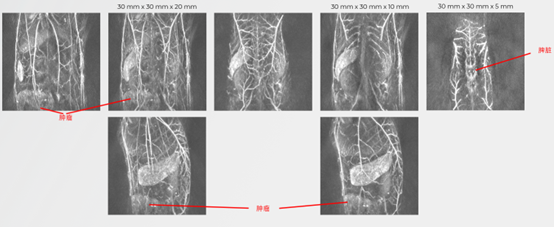

小鼠腫瘤組織監(jiān)測:

無標(biāo)記的小鼠腫瘤組織成像